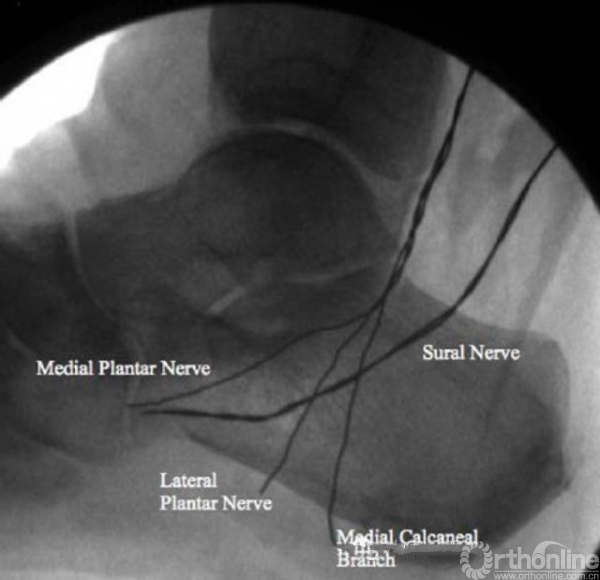

本研究选取了40只新鲜-冷冻的足标本,尸体平均年龄78.1岁,其中18男,22女。用可显影线绑定于腓肠神经、胫神经、足底内外侧神经上,然后行X线透视。观察各条神经和骨的关系。通过开放和经皮的跟骨截骨分别观察神经损伤以及神经和截骨平面的关系。